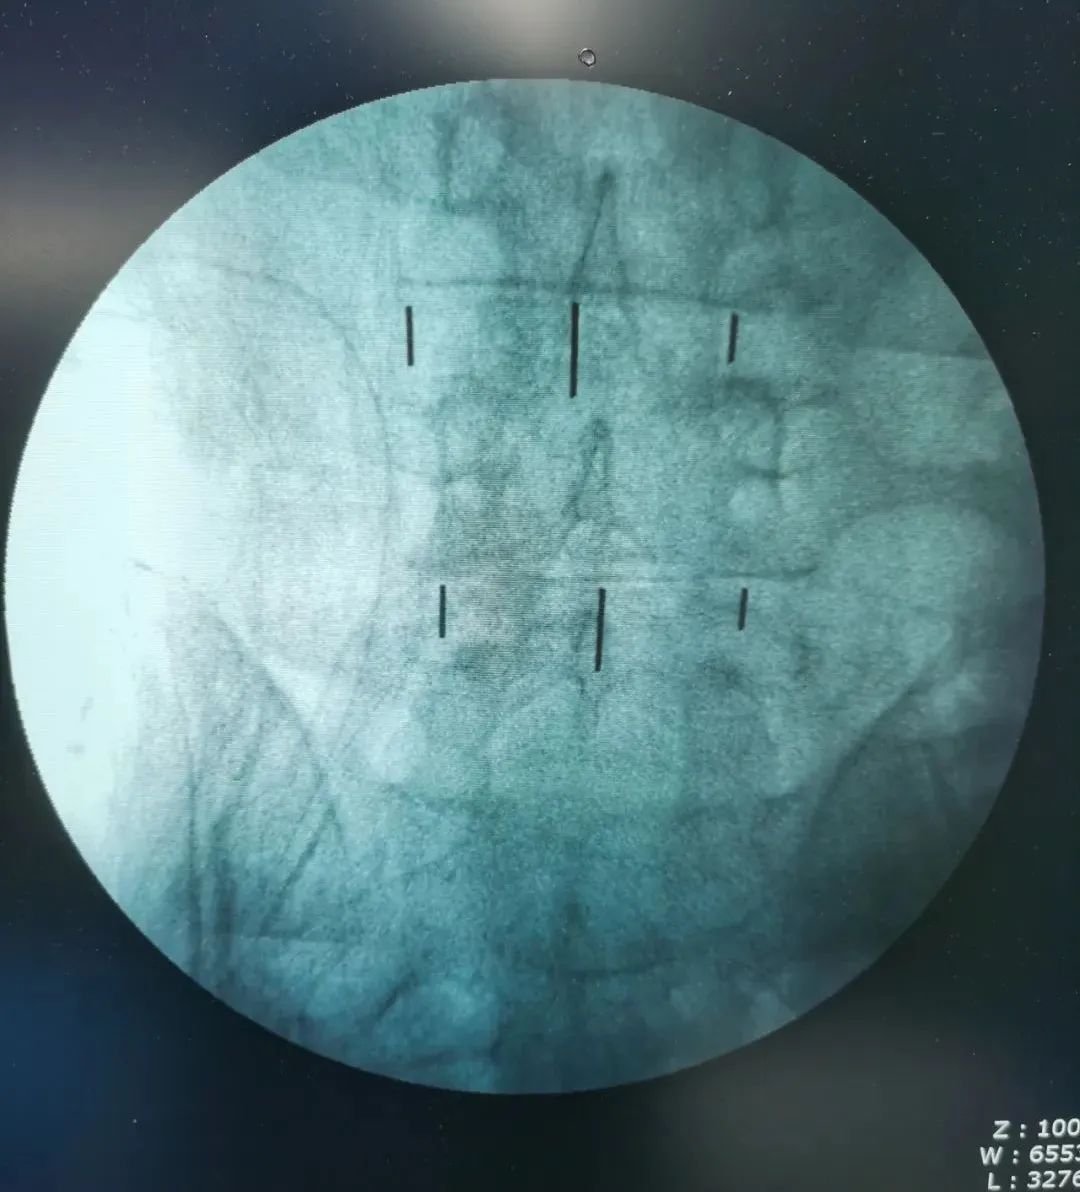

▲术中影像

神经脊柱科张少华主任、熊东主任接诊后,结合马先生的查体及其他各项检查结果,确诊患者为“腰椎间盘突出症”,在严格执行相关收治程序后,陕西冶金医院神经脊柱科将患者收治入院。在详细评估患者病情并与患者及家属充分沟通后,如期进行了椎间孔镜手术。

手术由熊东主任亲自操作,在内镜下精细操作,成功摘除了突出的椎间盘组织。术后,马先生的右腿疼痛明显缓解了,在神经脊柱科医护团队的精心照料下,第2天马先生就下床走路了,和术前走路的样子相比判若两人。